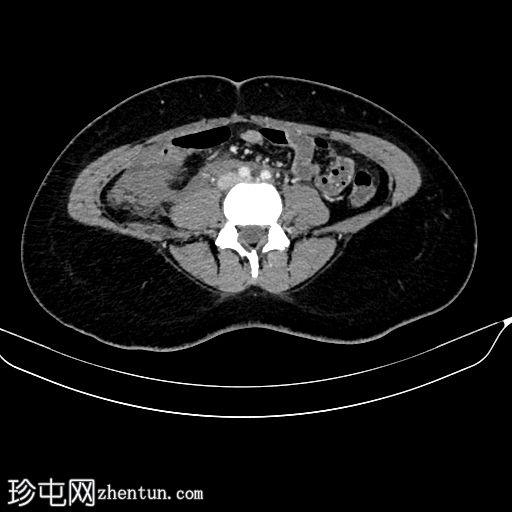

轴位

平扫

右肾周间隙可见高密度影(HU=65),经右侧结肠旁沟延伸至肾盂。

右肾上极区可见一较大、边界清晰、以脂肪密度为主、伴有实性强化成分的病灶,延伸至肾盂。

该病灶延伸至肾盂区域并推移肾盏;但未见侵犯或肾积水。

符合血管平滑肌脂肪瘤破裂的特征。